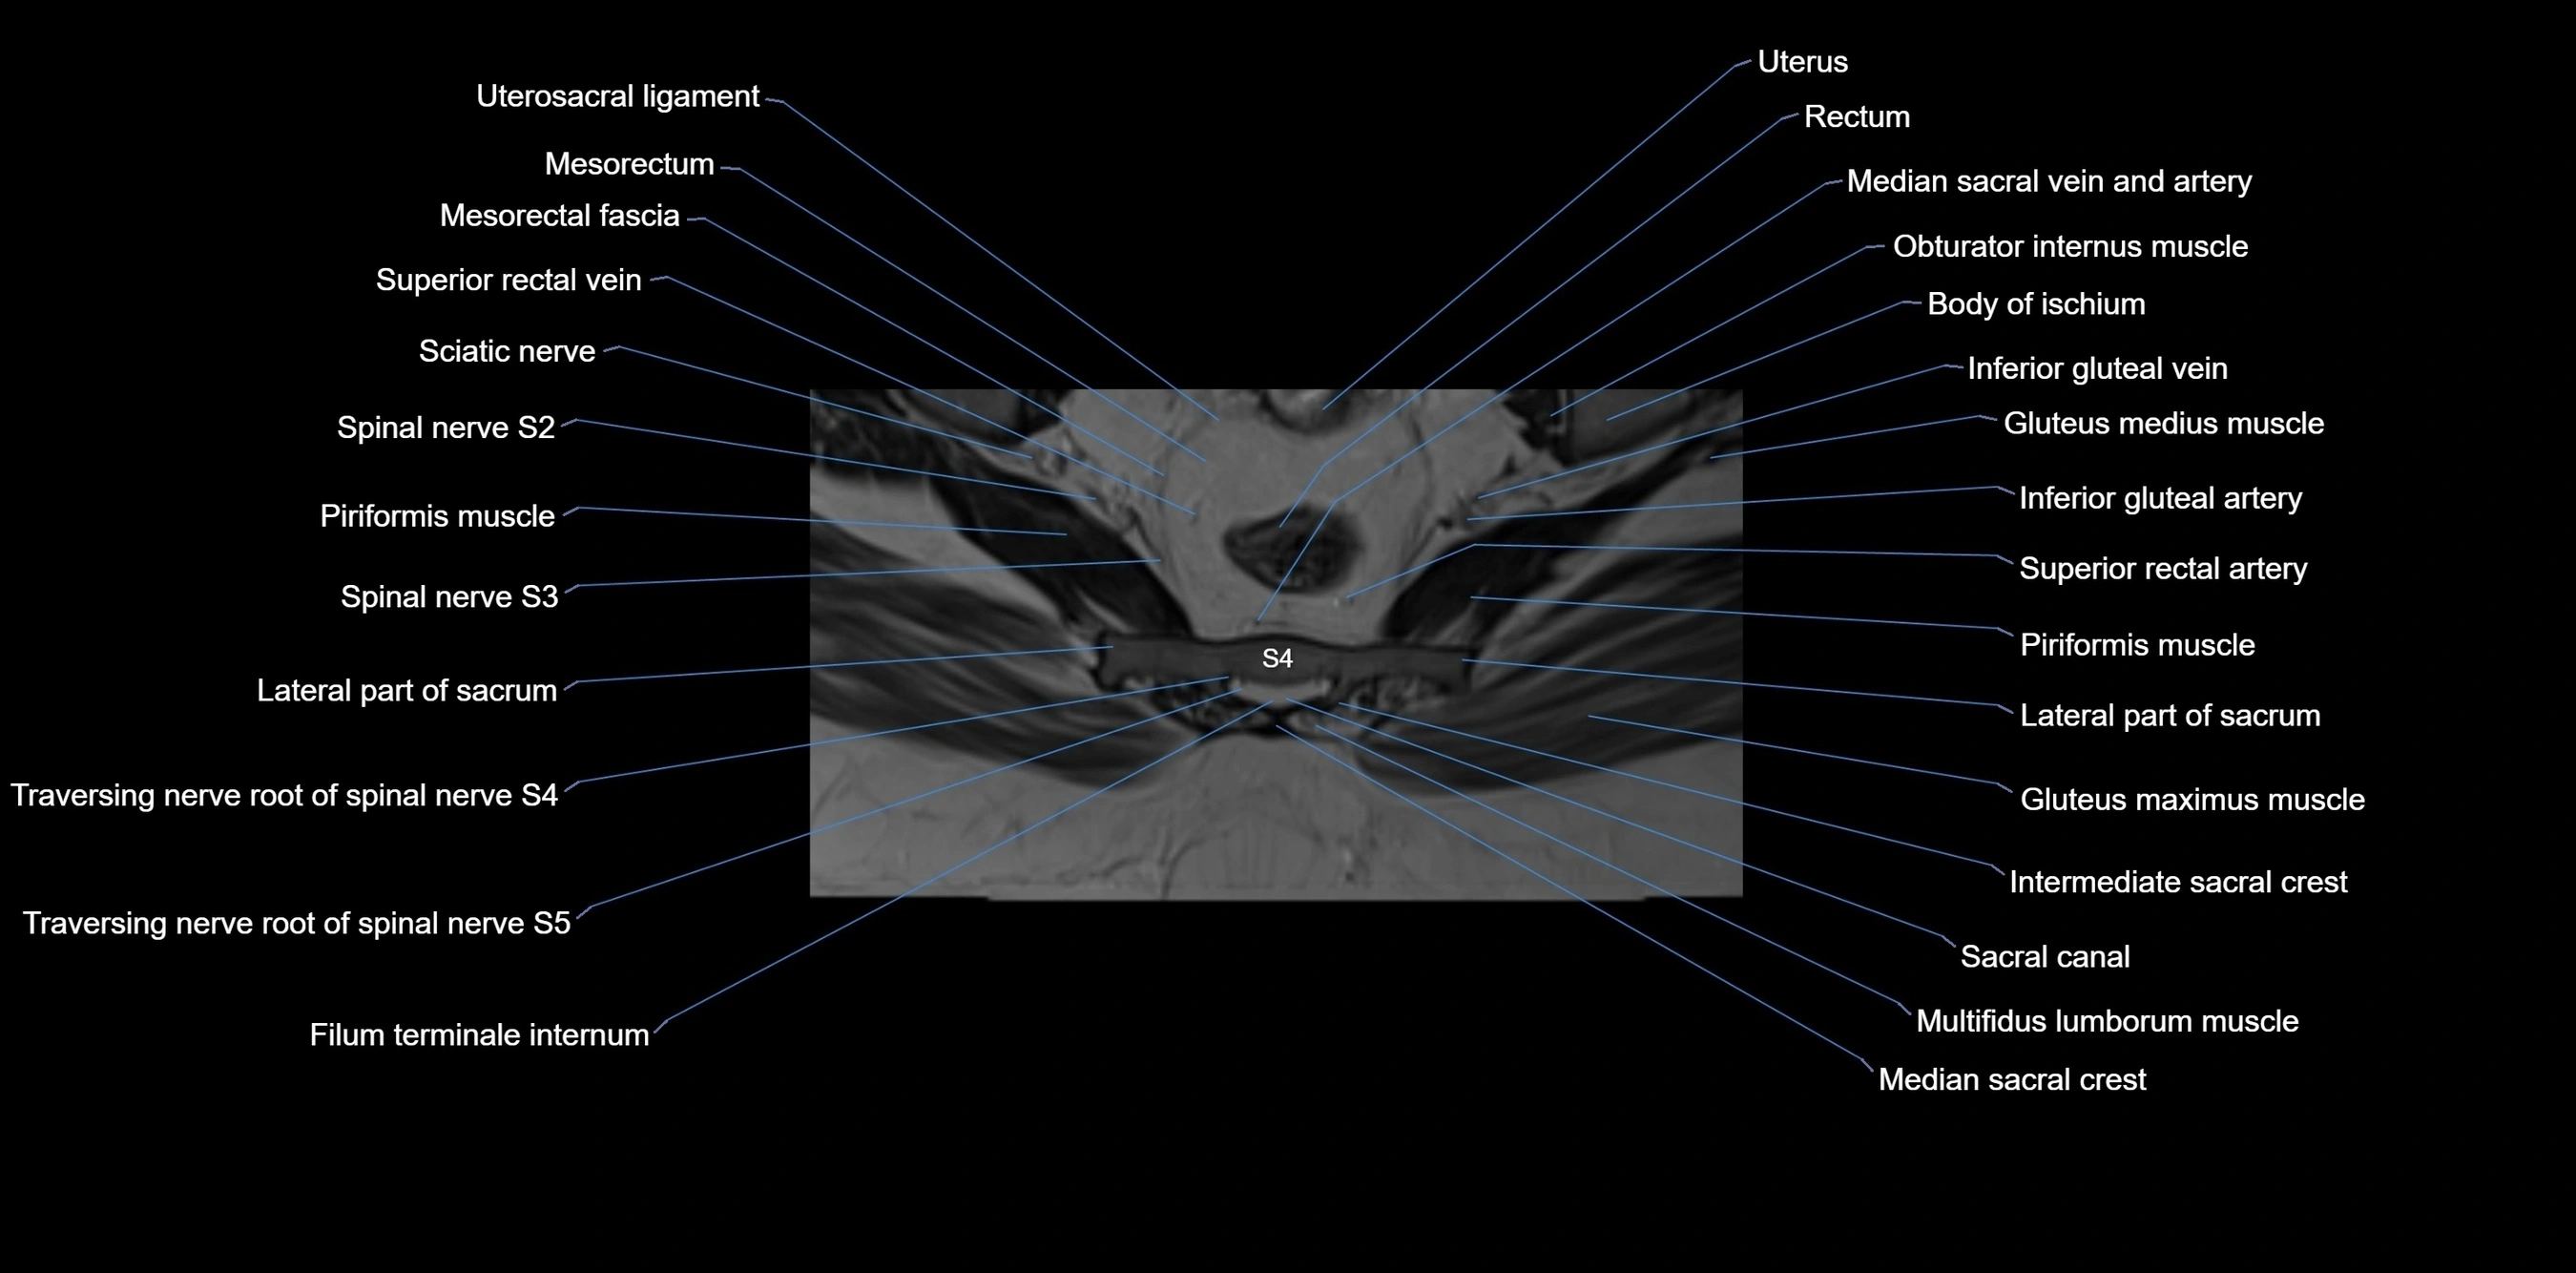

MRI image

image